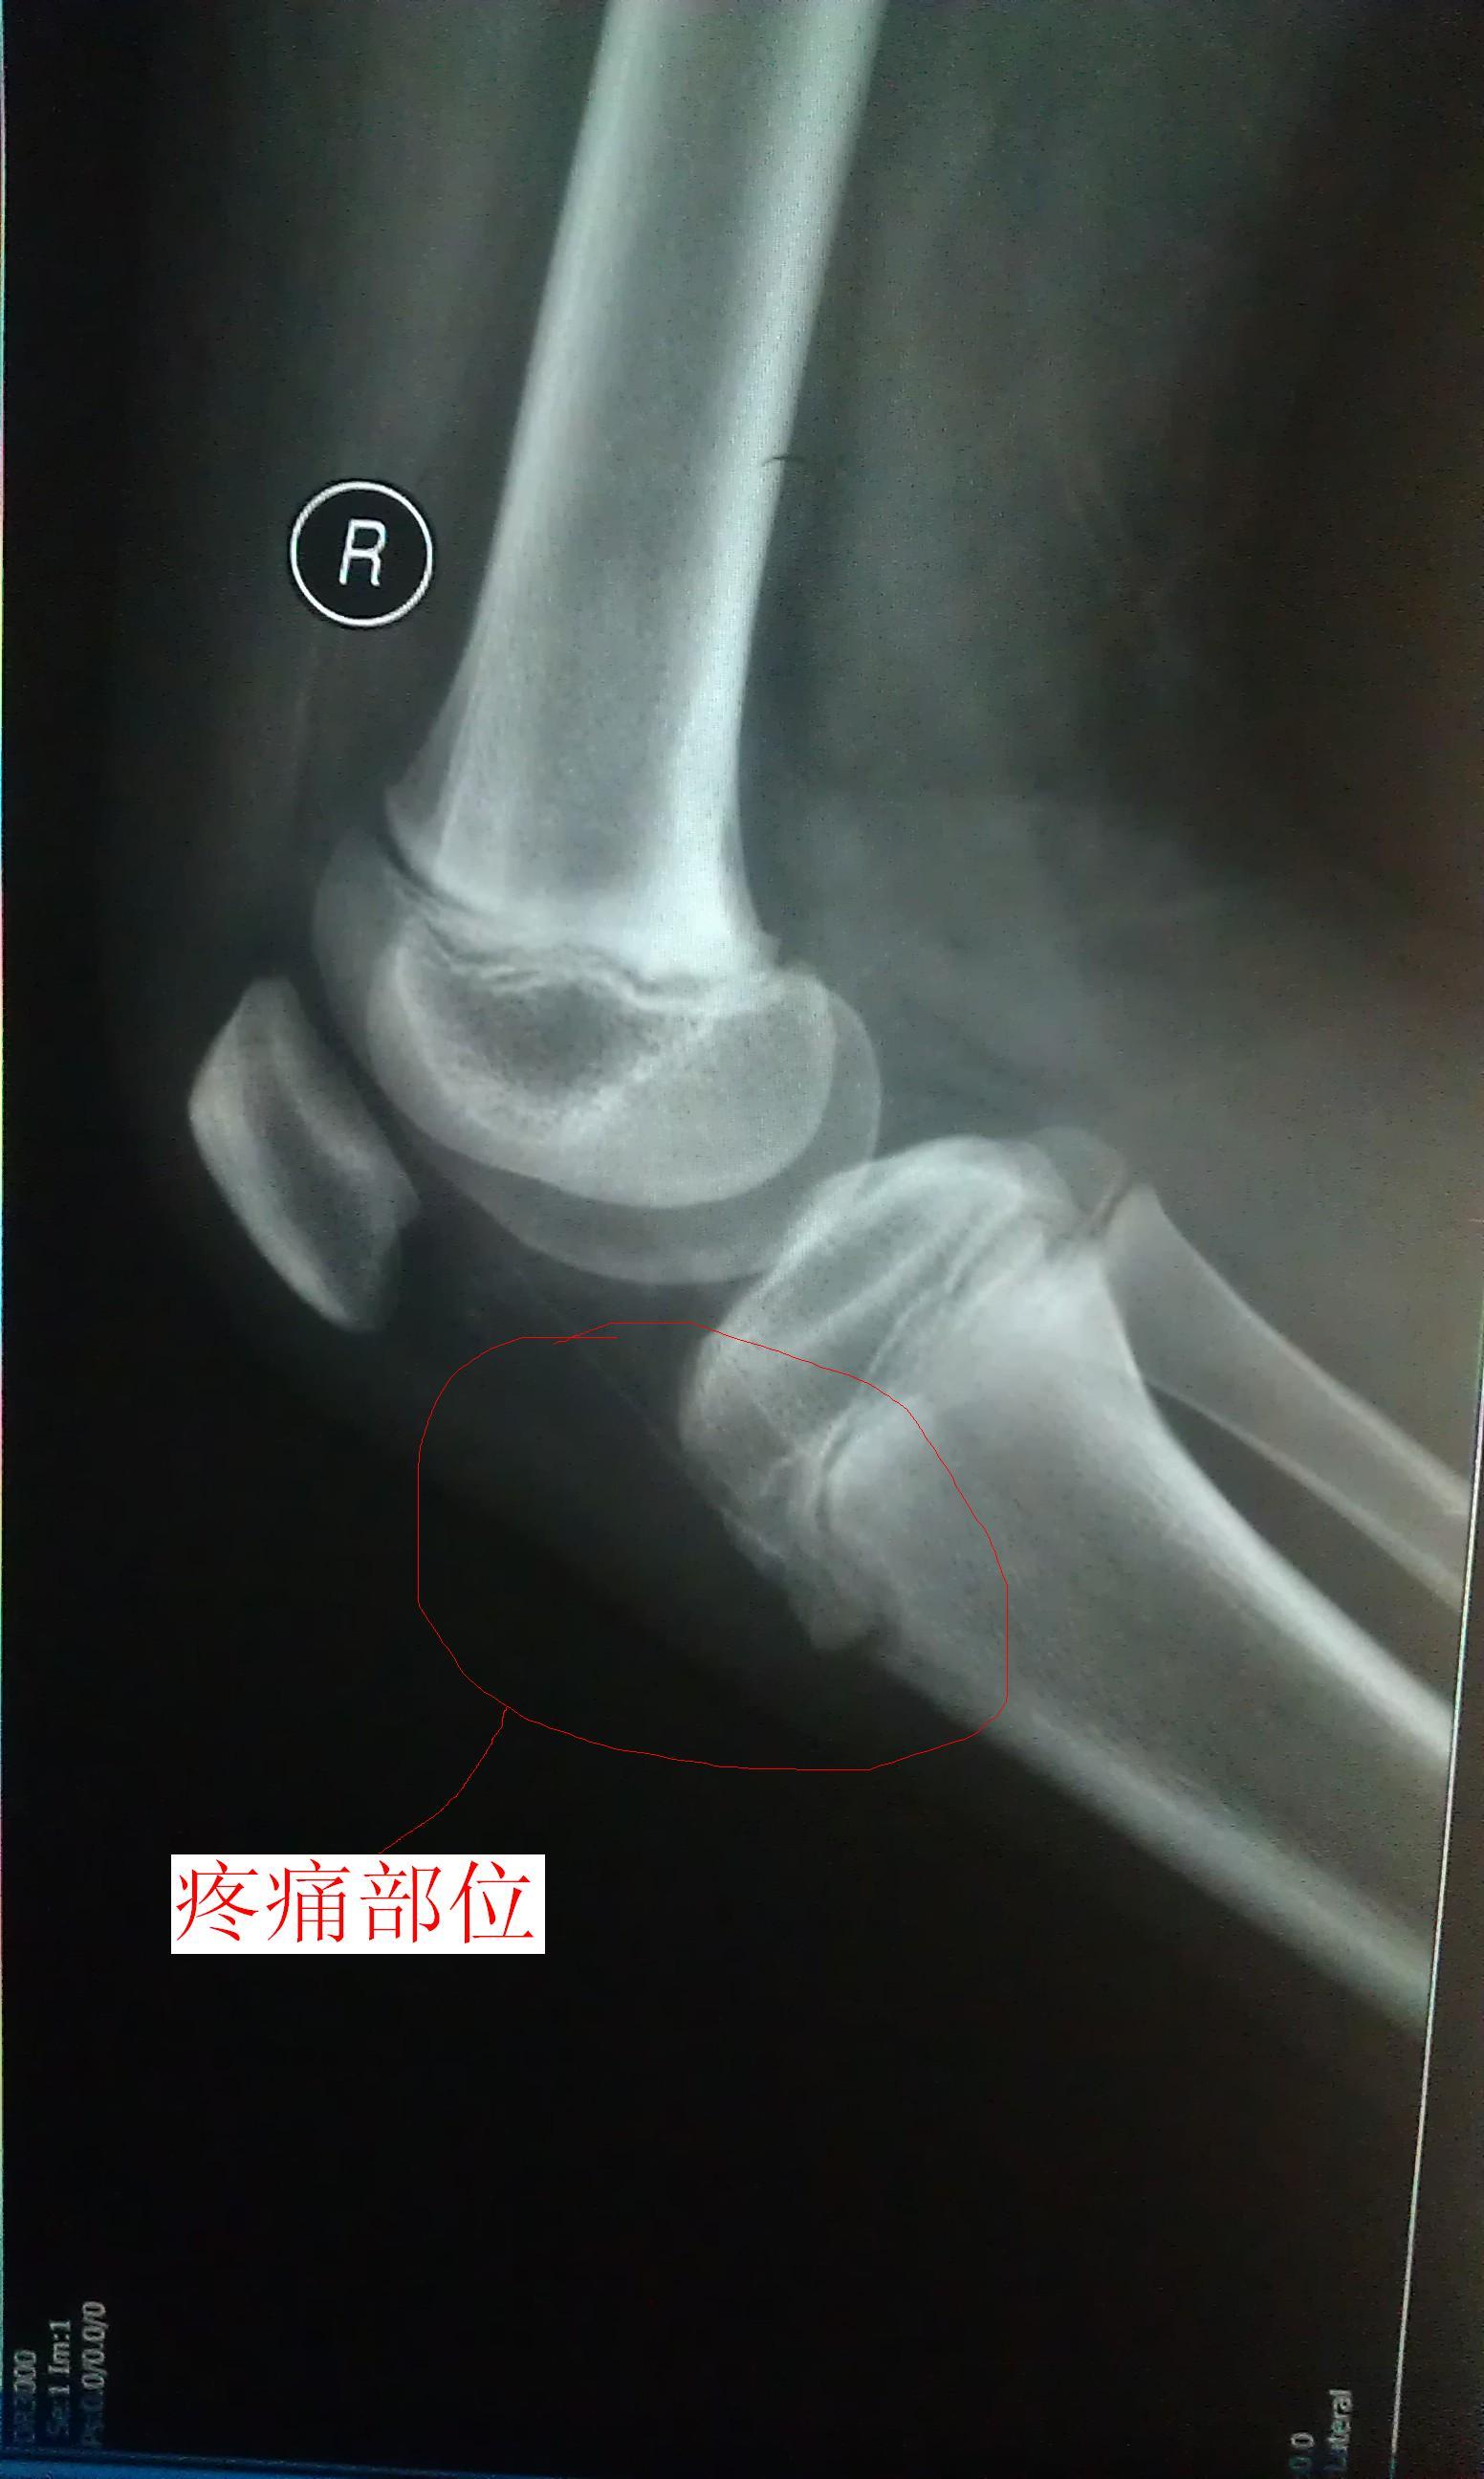

我小孩在近一个多月 下蹲 上站时 膝盖下面总是疼(按他说的意思我在图3标了一下),一开始是右腿,现

在是两条腿的相同部位都有这现象,一边疼的时候去医院看过,也拍了X片(见图1、2),医院医生没说什么,开了药和膏药,说吃完了还疼再去给他看,是不是风湿性关节炎(病历和药见图4)。我们家长不放心这医生,在这想请在线医生帮帮忙,分析一下我孩子的X片 !不胜感激!